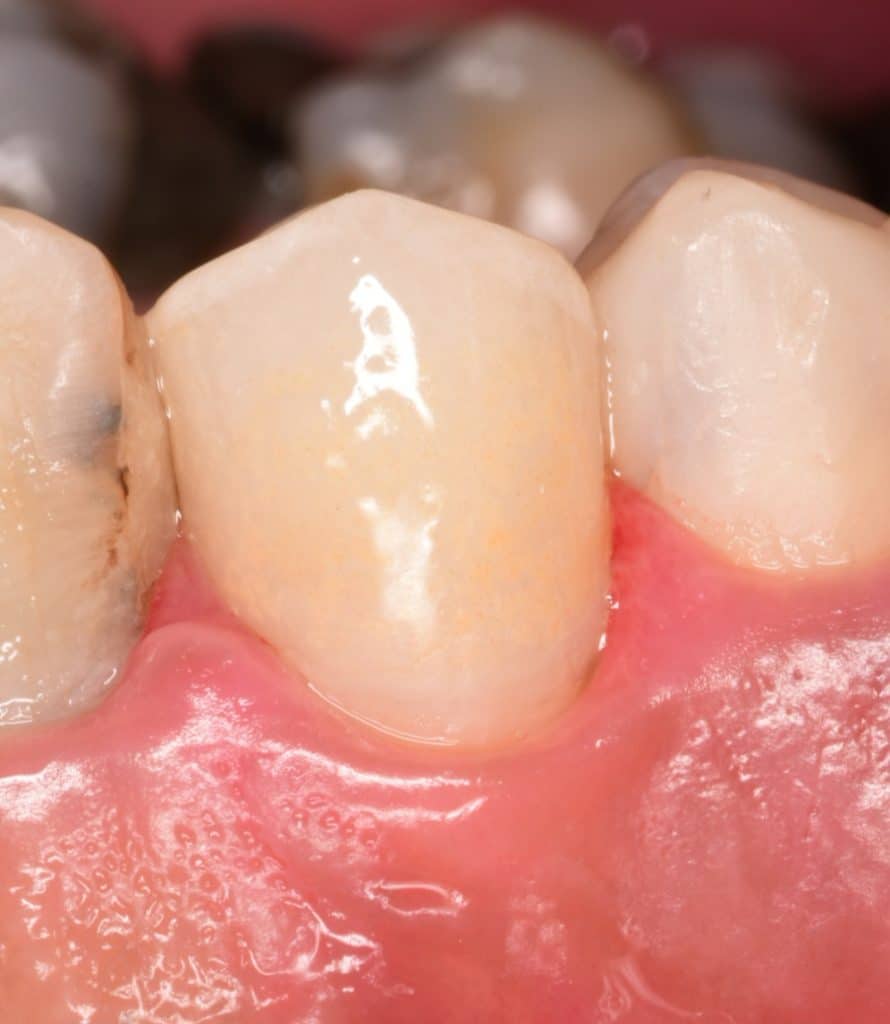

Buccal view

You can see the buccal extension of the preparation for more esthetic, this is the veneerlay preparation